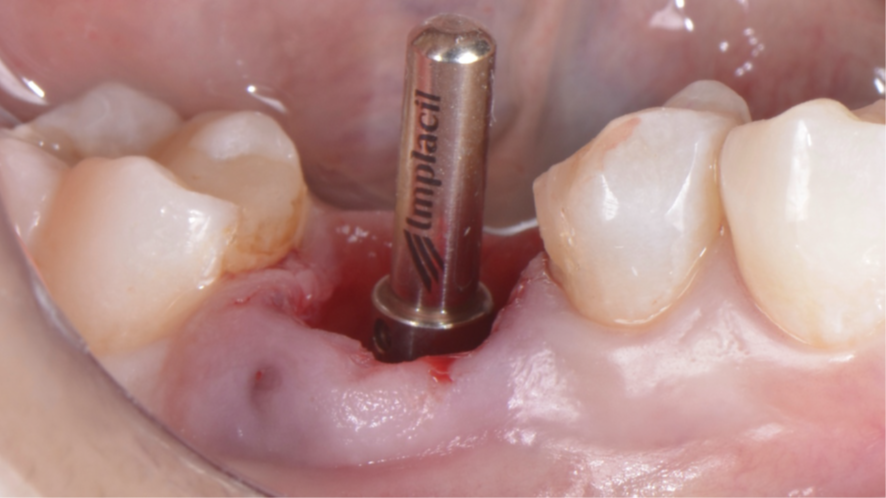

Mulher de 48 anos, sem antecedentes médicos relevantes, procurou atendimento odontológico com queixa principal de dor contínua em região do primeiro molar inferior direito. Na avaliação clínica foi observado uma fístula na vestibular do dente 46 (Figura 1) e a tomografia revelou uma fratura longitudinal, comprometendo a manutenção deste dente (Figura 2). Confirmada a necessidade de exodontia, foi planejada a instalação de um implante imediato e a confecção de um cicatrizador personalizado diretamente na plataforma do implante com um pilar provisório de titânio. Foi realizada uma extração dentária minimamente traumática visando preservar a integridade dos tecidos moles e duros circundantes (Figuras 3 e 4).